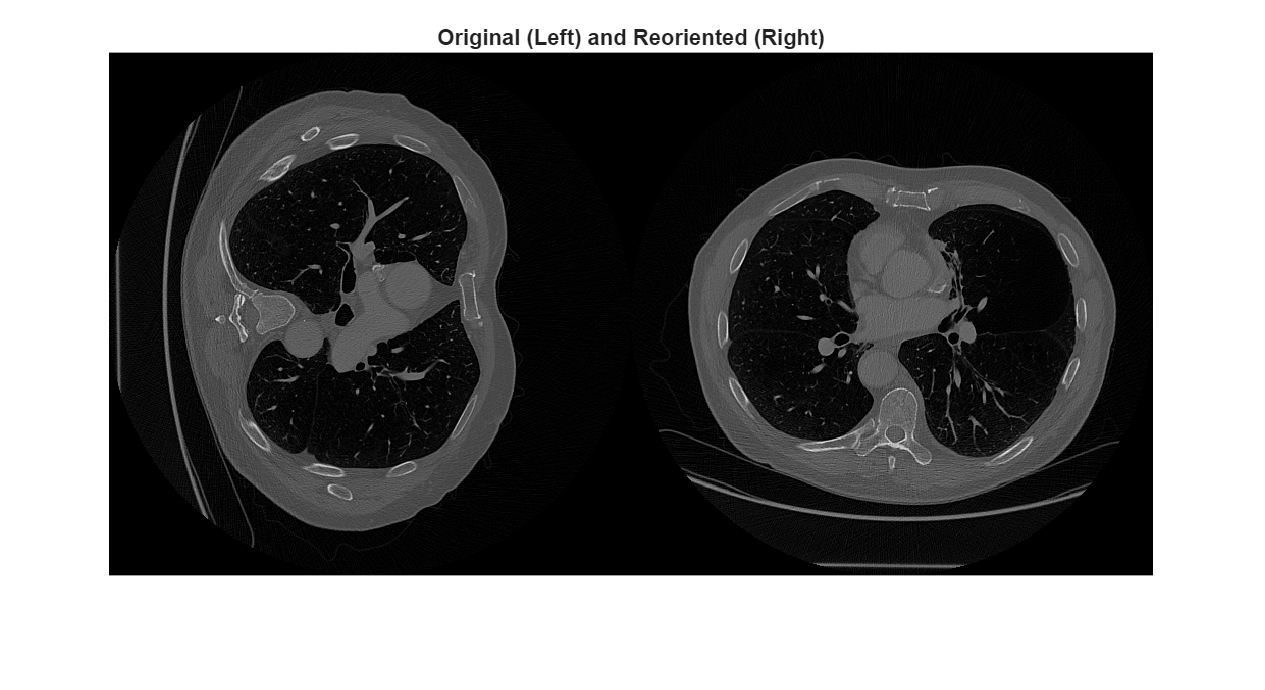

To observe the difference in the orientation between volumes, display a transverse slice from each volume in intrinsic coordinates. Display intrinsic coordinates by indexing into the Voxels property.

sliceOriginal = medVol.Voxels(:,:,150); sliceReoriented = medVolReoriented.Voxels(:,:,150); imshowpair(sliceOriginal,sliceReoriented,"montage") title("Original (Left) and Reoriented (Right)")

When you display images using functions like imshow and imshowpair, the column indices increase as you move left to right in the display. Therefore, when you look at the patient position within the images, columns increase anteriorly for the original volume slice and to the right for the reoriented volume slice.